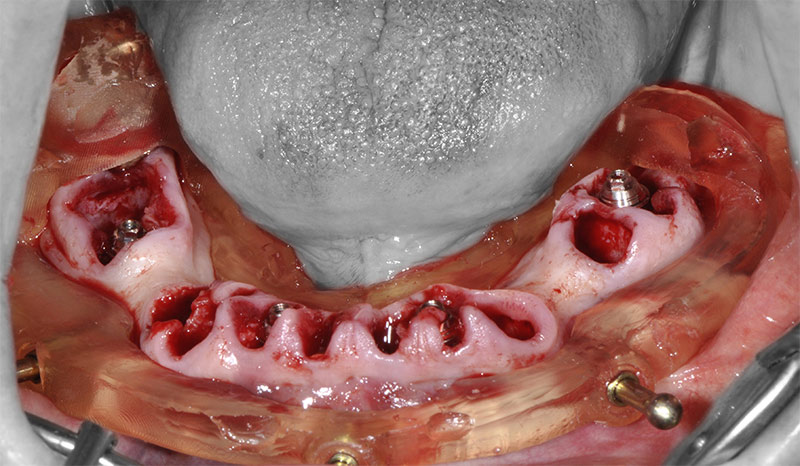

Fig. 28 : le guide de forage et d’insertion des implants est empilé sur le guide de résection laissé en place.

Fig. 29 : toujours sans toucher au guide résection, une fois les implants mis en place, les piliers prothétiques sont vissés.

Fig. 30 : enfin, la restauration transitoire est empilée sur le guide de résection pour être solidarisée en bouche aux gaines provisoires vissées sur les piliers.

Fig. 52 : le guide de forage et de mise en place des implants est empilé sur le guide de résection osseuse.

Fig. 53 : vissage des piliers prothétiques dans les implants.